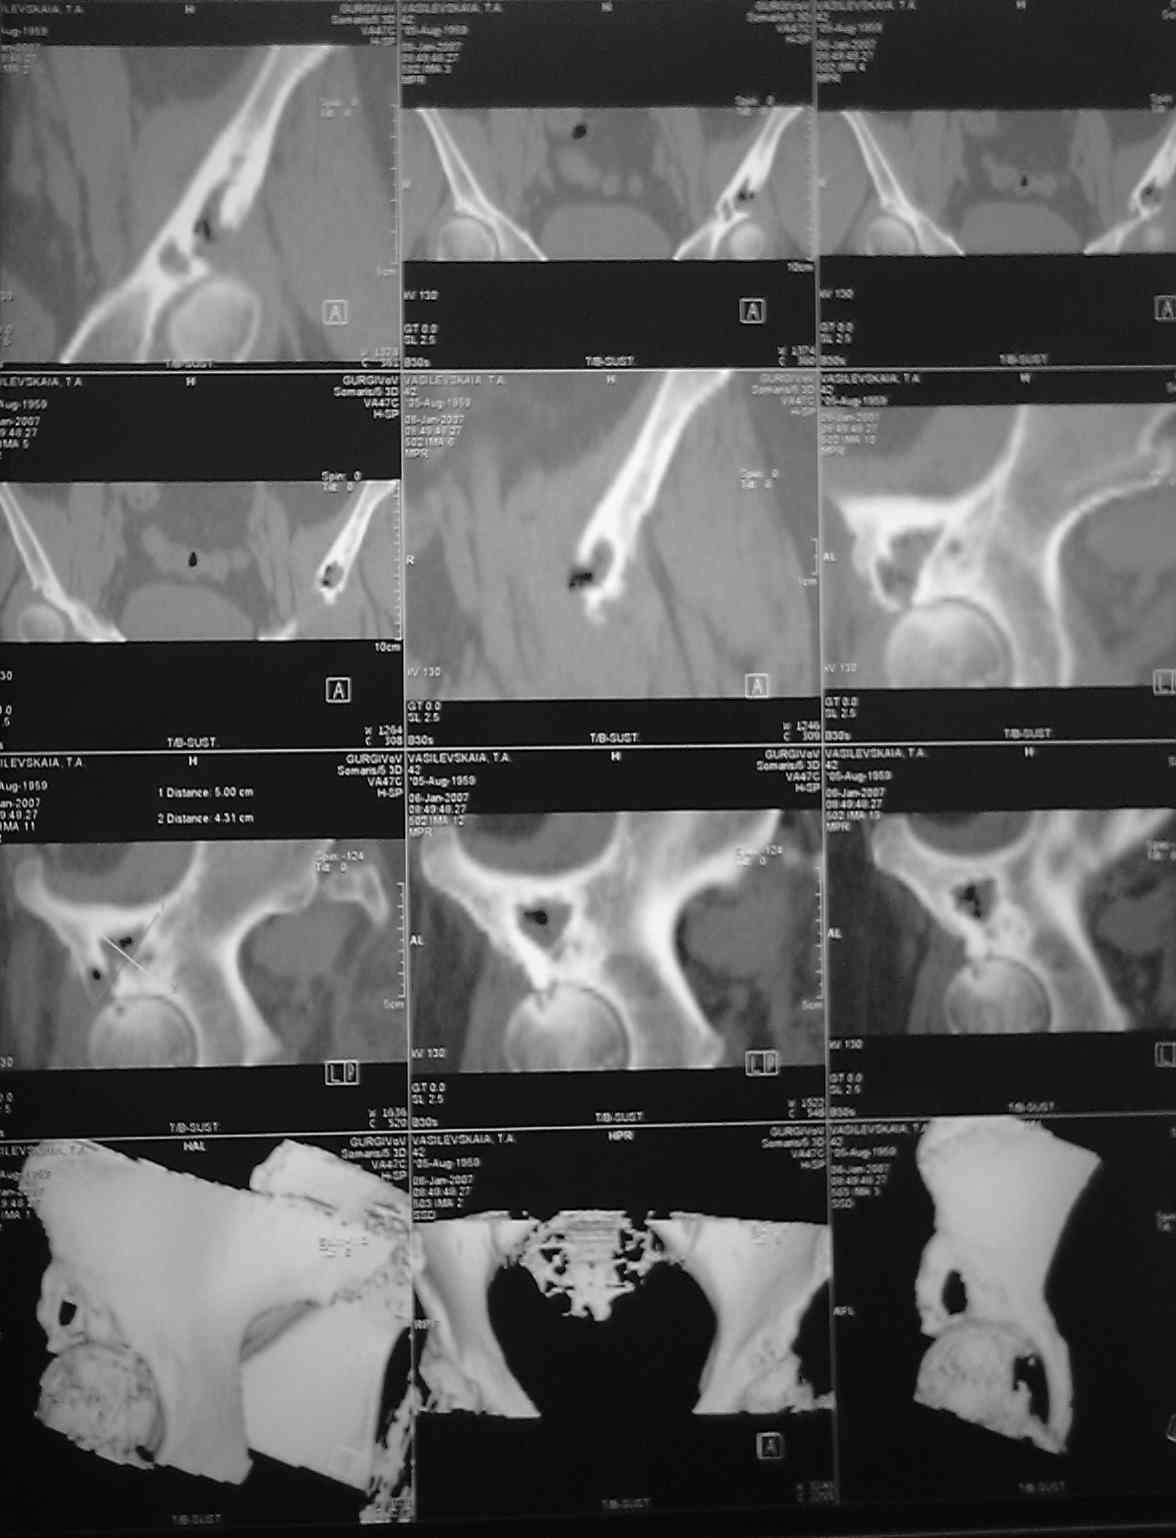

Коллеги .пожалуйста помогите. Представляю КТ нашей операционной сестры.Боли в тазобедренном суставе беспокоят около 2-х лет.В последние2-3 месяца боли усилились, хотя интесивность была умеренная. Продолжала работать проводя,в операционные дни, стоя, по 7-8 часов.Рентгенологом (очень предположительно) выставлен диагноз-туберкулез. Я даже предположительно затрудняюсь поставить диагноз, но, по-видимому, без операции с экспресс-биопсией не обойтись, иначе исход в патологический перелом с центральным вывихом. Три вопроса: 1)Что это? 2)Где лечится? 3)цена вторго вопроса? Больная - гражданка РФ и жена старшего офицера запаса, так что право на лечение в госпиталях МОРФ вроде бы имеет. Но мед. страховки нет. У нас ее просто не выдавали. Заранее благодарен, как я, так и коллектив хирургического отделения.(госпиталь МО г.Тирасполь)

Вы уже не первый из участник не представляющий ничего кроме картинок КТ. Покажите, пожалуйста, обычные рентгенограммы, анализы и подробно изложите жалобы и анамнез. Первое, что приходит в голову - остеомиелит и туберкулез. К сожалению дифференциальная диагностика этой патологии в костях таза очень сложна и иногда окончательный диагноз удается поставить только после операции, т.е. он не всегда совпадает с данными экспресс-биопсии. Ее спешить делать не советую до тех пор пока не решите где и когда больная будет оперироваться, т.к. высока вероятность формирования свища и перекрестного инфицирования. Уточните, действительно-ли пациентка имеет право на лечение в госпиталях МО РФ (об этом должна быть печать в пенсионном удостоверении у мужа), если "да" - сброшу адреса для запросов на перевод.

Александр, покажите для наглядности обзорные Ртг таза,а то что-то на седалищную кость не похоже, а второй сустав явно диспластичный. Что примечательного в крови и в клинике указывает на новообразование или специфич. инфекцию?

1)На Рождество надо верить в лучшее :-)Мы наблюдали такие первичные изменения костной ткани без признаков поражения суставного хряща и без сообщения с полостью сустава, которые вынуждали проводить дифф. диагностику с гиг.кл.опух., пигм.вилонод.синов., mts, фибр.диспл., внутрикостн. гангл., атипичн. остеомиелитом. Однако гистол. содерж. полости у таких больных после ТЭП давало только наличие костн. ткани или хряща с явлениями некроза и умеренного хрон. воспаления. Ни скоплений грибов, ни роста микробной флоры. Расценивали как проявление дегенеративно- дистр. поражения с первичной (в "защиту" клас. Косинской)кистозной перестройкой кости в стресс-центрах .При таком относительно благоприятном варианте (2-3) имеет множество решений. В остальных случаях место лечения надо выбирать.

Спасибо всем,кто откликнулся, высылаю

обзорные снимки таза. Прошу извинения за качество снимков

Ну что уж извиняться, лучше повторить Ртг :-), да и клинику уточнить с акцентом на предыдущ. вопросы. Если нет признаков воспаления - почему не стрессовая киста?